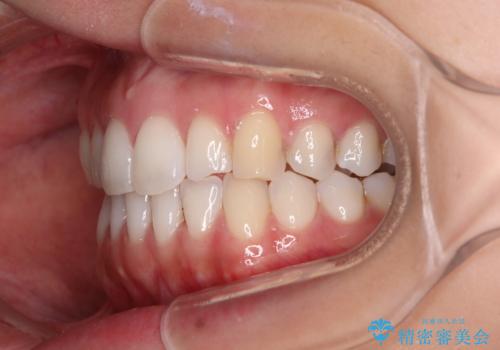

前歯の重なりをインビザライン・モデレートで矯正治療

- 上下前歯の重なりを気にして来院された患者様です。

安価なインビザラインパッケージを用いての治療を希望されており、デコボコの程度が中等度であったため、インビザライン・モデレートを用いて矯正治療を行うこととしました。

インビザライン・モデレートは、製作できるアライナーの枚数に制限があるため、移動可能な量に限りがあるものの、インビザライン・ライトよりも枚数が多いため、幅広い症例に対応可能です。